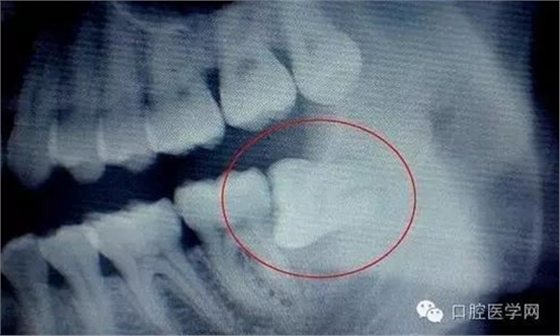

牙齒萌出困難稱為"阻生齒"或"埋伏牙"。阻生齒最常見(jiàn)于下頜第三磨牙,此牙萌出年齡在20歲左右,故稱為"阻生智齒"。阻生智齒會(huì)產(chǎn)生下列危害:

(3)第二磨牙齲壞:向前傾斜的阻生智齒,因經(jīng)常在鄰牙間積存食物,易發(fā)生鄰牙(下頜第二磨牙)齲壞。